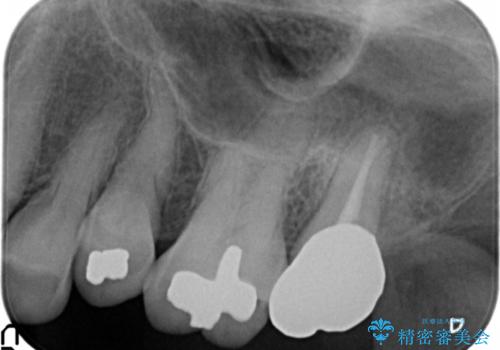

- 根管治療ののち、そのままになっていた歯のクラウン製作を希望され来院されました。

クラウンの将来的な虫歯の再発を防ぐために周囲の歯ぐきを切除することで歯の高さを出し安定した歯周環境にしたのち噛み心地の良いゴールドクラウンを製作します。

クラウンを装着した歯の虫歯の再発を防ぎ長い予後を期待するために削った箇所をしっかりとかぶせる適合の良さが必要はもちろんですが、セメントの漏洩を防ぐためにクラウンの十分な支台高径を歯周外科を行い獲得しました。